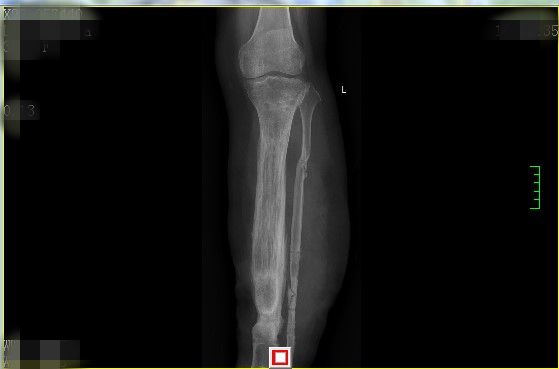

术前患者左侧胫腓骨粉碎性骨折

骨搬运术后2年去除外固定装置左胫骨骨缺损(约18cm)两端成功合拢,生长良好